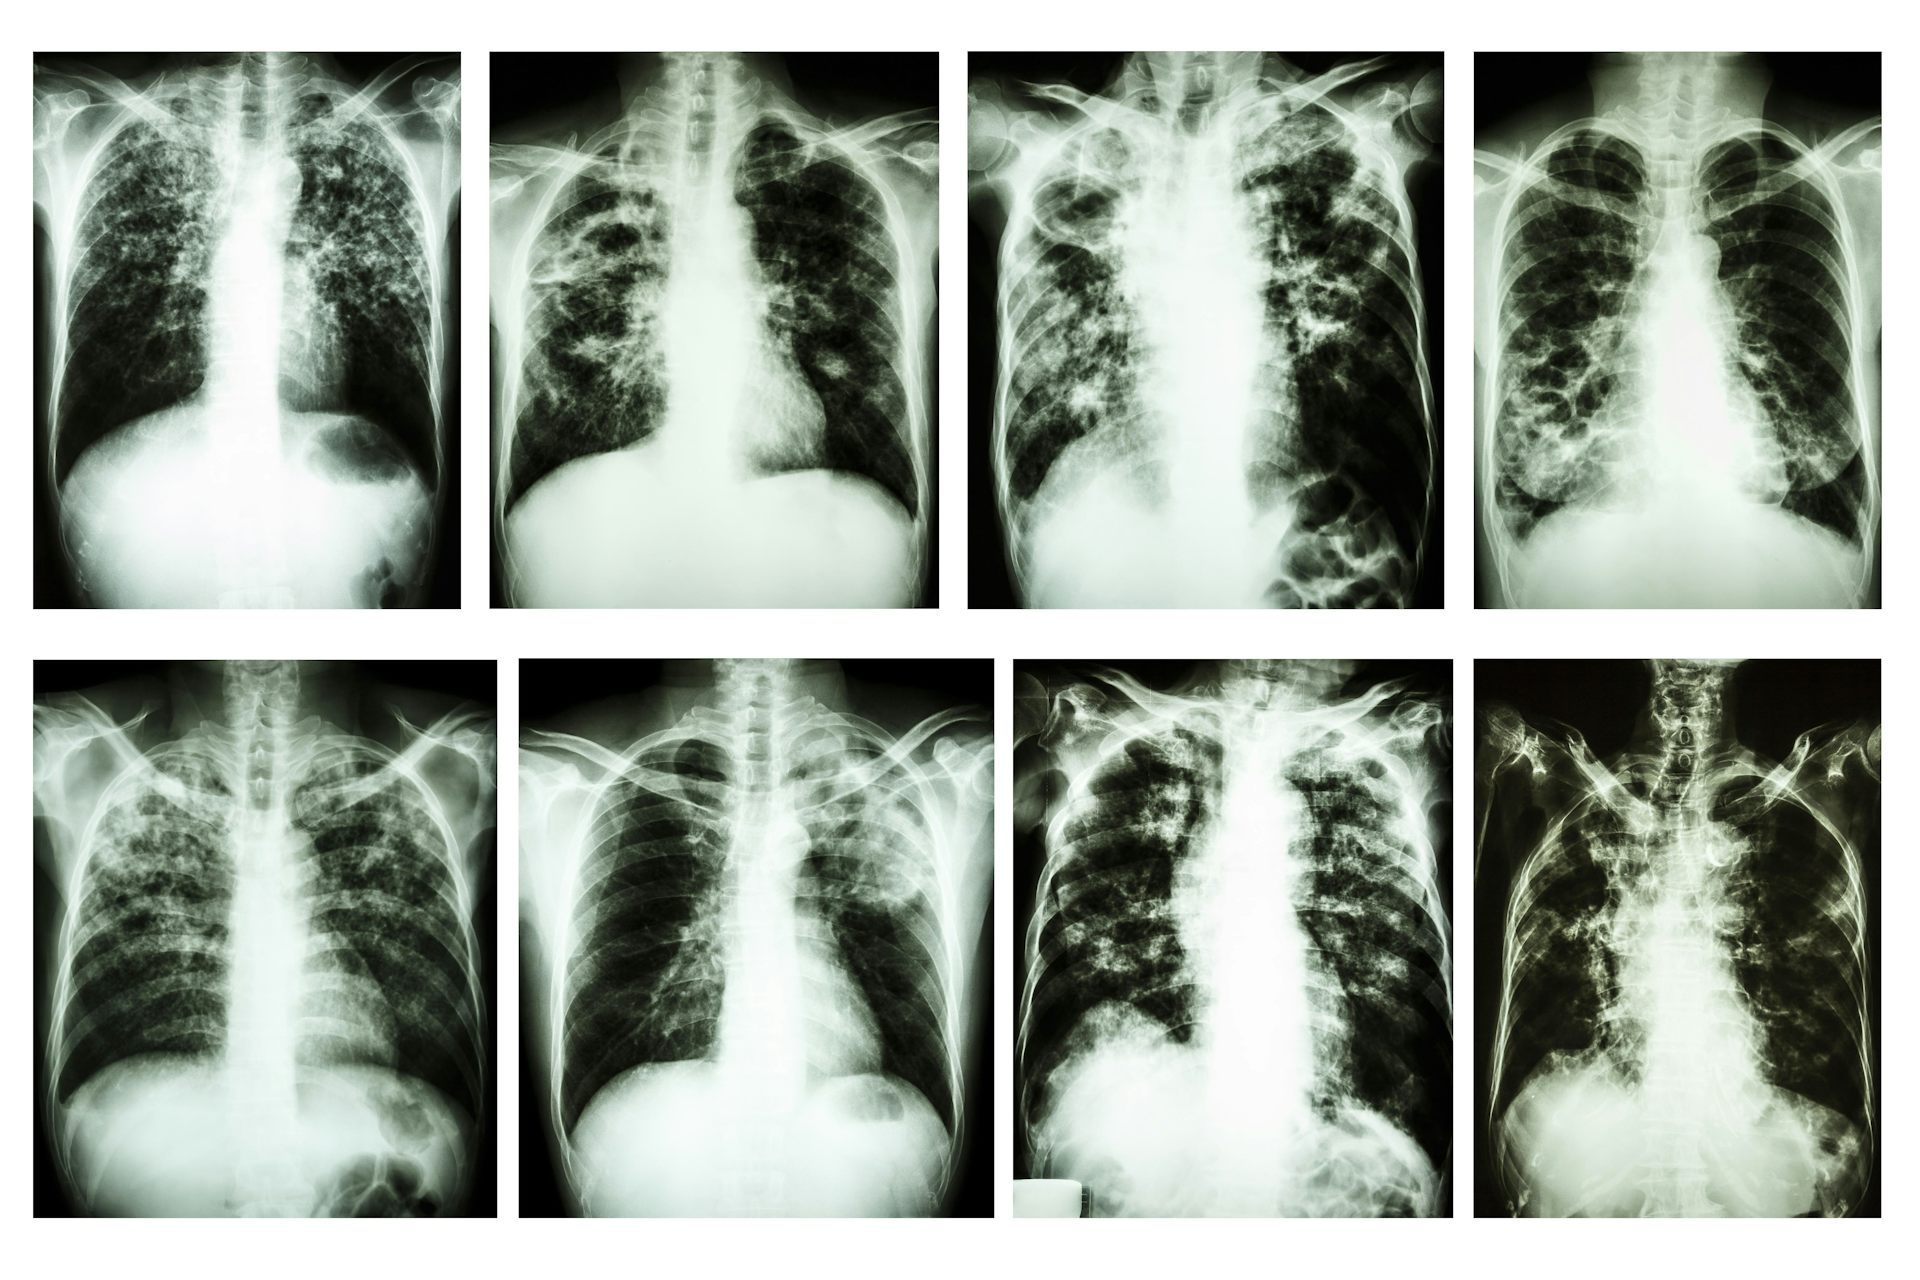

Как выглядят руки при туберкулезе - фото презентация